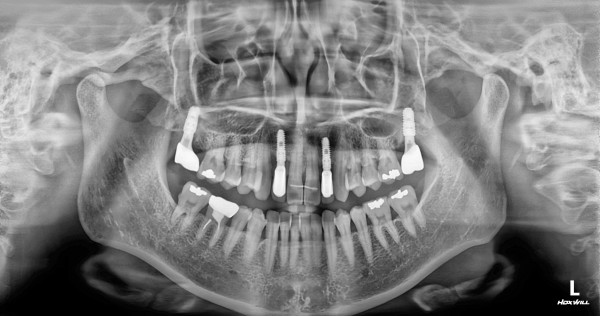

임플란트 센터 | 여) 41세